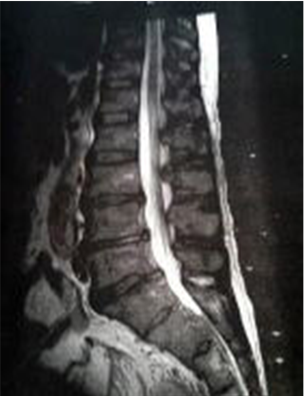

当院では、画像での診断も行っております

病院からレントゲン画像やMR画像を持参いただけるとより詳しい判断ができます。医師や医療関係者、他店の整体師や柔整師が自分の身体のメンテナンスのために来店する当院。宇都宮市の病院内で院長自ら施術をしていた経験もあり「安心」と「信頼の技術」が人気です。